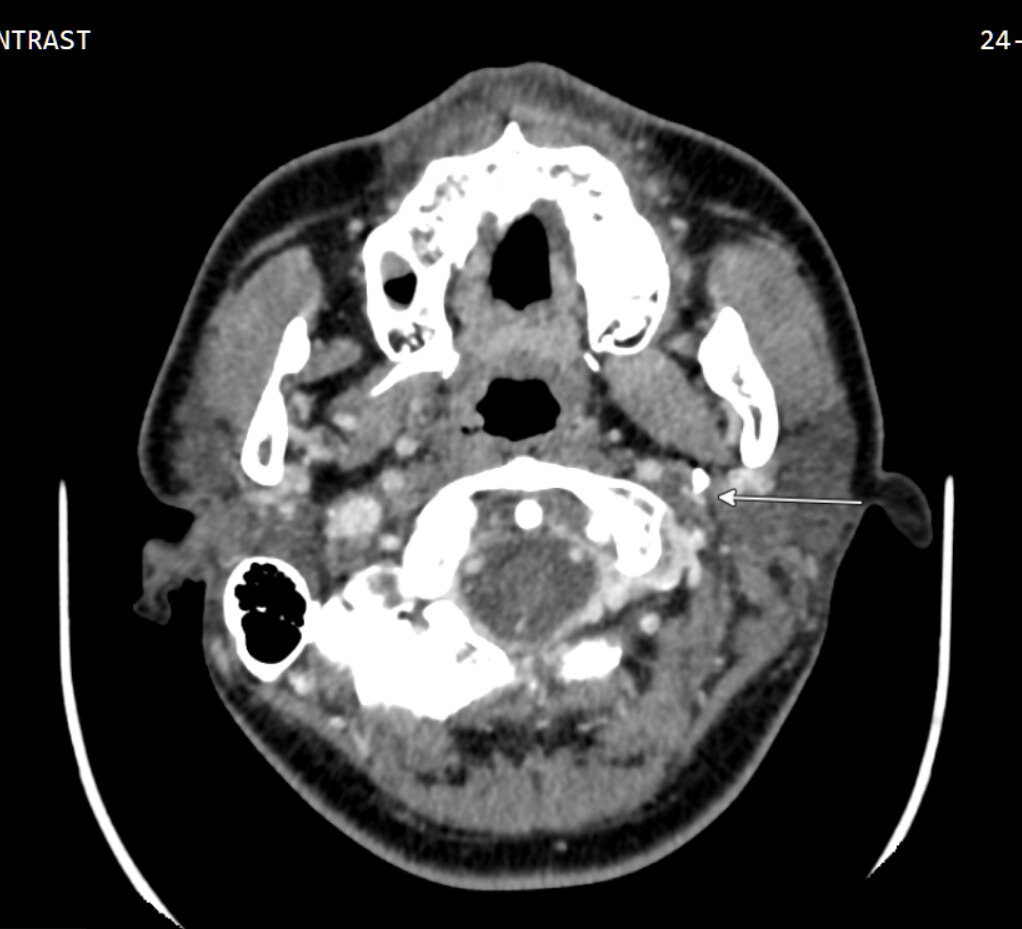

So in 2023 I went to Bellevue ENT, did a CT scan and got a diagnosis of possible Eagle Syndrome, because my styloid process is mildly elongated. But I hesitated to consider surgery because the symptom is not that bad. But in 2025 I finally decided to go to UW medical center and I am currently with Dr. Merati.

After the first visit, I tried speech therapy, which didn’t help at all. I just had my 2nd visit, and the doctor said there were 3 causes he knew of: 1) reflux from stomach (which I do have) 2) nerve damage 3) Eagle syndrome. He is not convinced it’s Eagle syndrome yet, because my left side is longer yet my problem is on the right side.